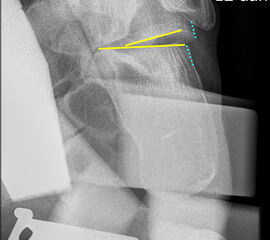

Stressaufnahme des oberen Sprunggelenks lateral

Position:

• Patient in Seitenlage auf dem Röntgentisch, zu untersuchender Fuß unten und seitlich auf der Röntgenkassette liegend (Achse des Fußes parallel zum Zentralstrahl).

• Zentralstrahl mittig auf das obere Sprunggelenk fokussiert.

• Film horizontal auf dem Röntgentisch.

• Röntgenröhre 0° vertikal.

• Der Fuß liegt in der Haltevorrichtung (z.B. Telos-Gerät, Scheuba-Apparat). Die Ferse wird von dorsal stabilisiert.

• Von ventral wird über die Tibia ein kontrollierter Druck von bis zu 15 daN (Dekanewton, entspricht ca. 15 kg) aufgebaut.

Kennzeichen des Röntgenbildes:

• Laterale Abbildung des oberen Sprunggelenks.

• Beurteilung der Translokation des Talus nach ventral (Talusvorschub).

• Gemessen wird die Verschiebung der Tibiaachse gegenüber der Talusachse.

• Als pathologisch gelten Talusvorschub > 2 mm im Seitenvergleich oder absoluter Talusvorschub > 4 mm.

Besondere Bemerkungen zum Beispielbild:

• Abbildung des oberen Sprunggelenks lateral.

• Fremdkörper in den plantaren Weichteilen in Höhe der plantaren Begrenzung des Kalkaneus.